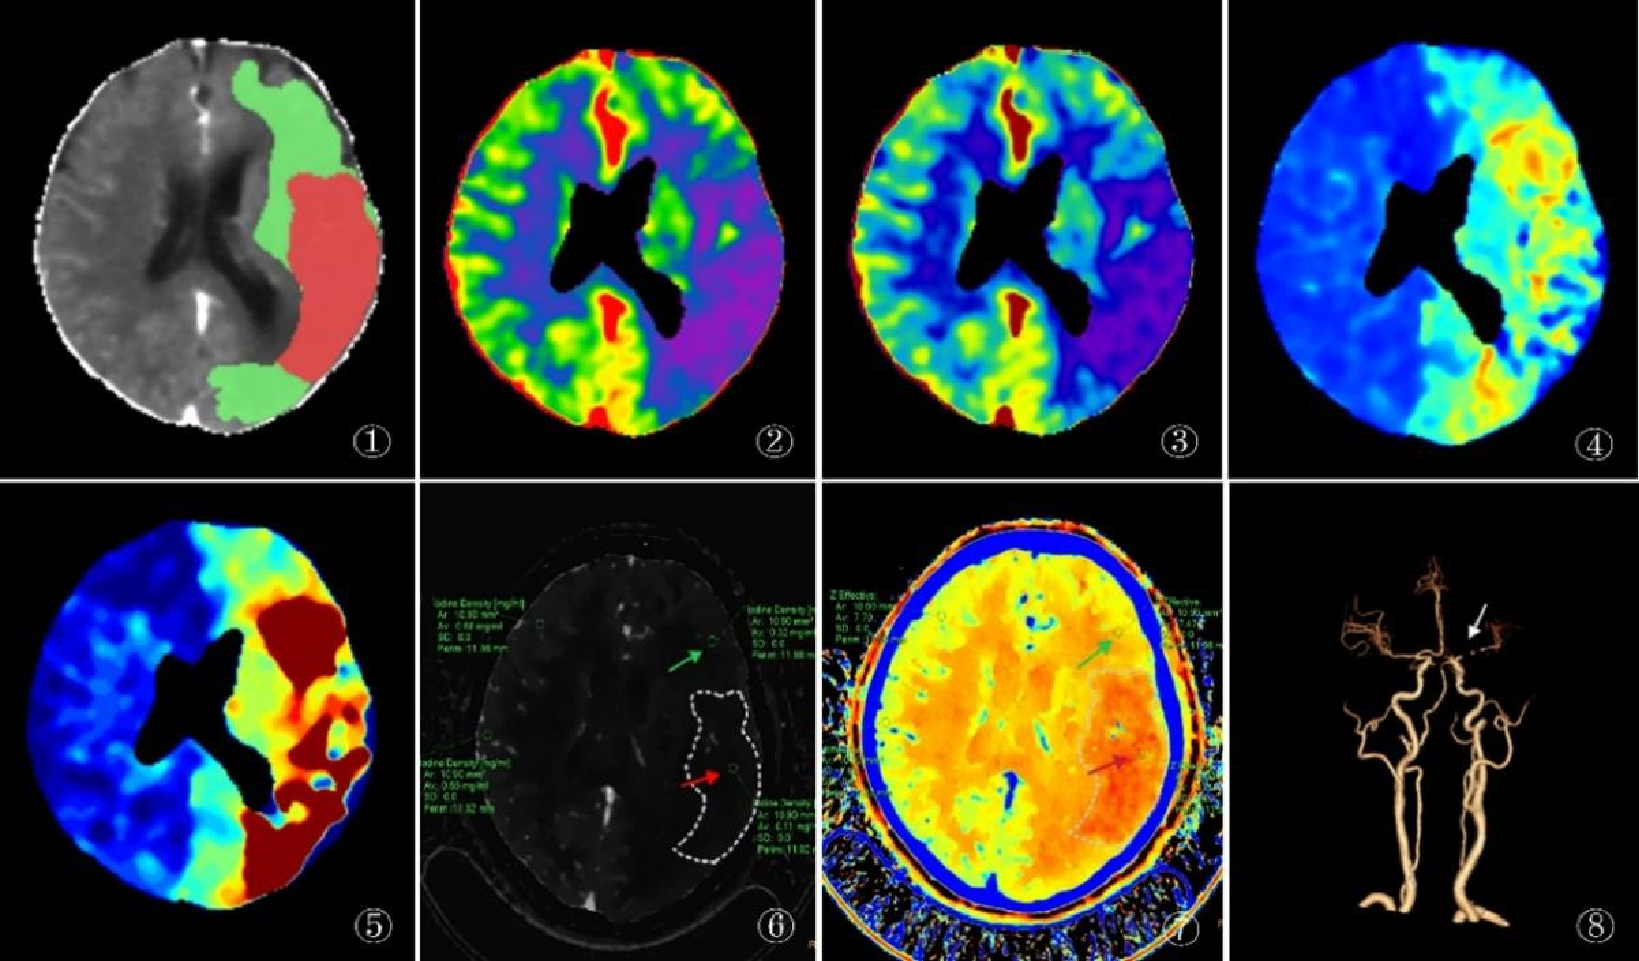

1.2 仪器与方法采用荷兰Philips公司IQon Spectral CT机对患者进行头颈部CTA及颅脑CTP成像。图 1展示了一名72岁女性患者入院后典型急性缺血性脑卒中的CTP和光谱CTA图像。

| A为CTP后处理得到的像,红色区域提示梗死核心,绿色区域提示半暗带;B~E分别为CTP的脑血流量(CBF)、脑血容量(CBV)、平均通过时间(MTT)、脑血流残余功能达峰时间(Tmax),CTP参数像显示左侧大脑半球呈低灌注改变,CBV、CBF较对侧减低,MTT、Tmax较对侧延长;F、G分别为光谱CTA碘密度与有效原子序数,显示左侧大脑半球灌注缺损,可见梗死核心区(红色箭头)及半暗带区(绿色箭头)的碘密度值分别为0.11 mg/mL、0.32 mg/mL,显著低于对侧正常脑实质区域的0.65 mg/mL、0.68 mg/mL,梗死核心区及半暗带区的有效原子序数值分别为7.33、7.47,显著低于对侧的7.68、7.70;H为CTA像显示正常大脑中动脉M1段重度狭窄、闭塞,其分支稀疏(白色箭头) 图 1 急性缺血性脑卒中患者的CTP和光谱CTA图像 Fig 1 CTP and spectral CTA Images of acute ischemic stroke patients |